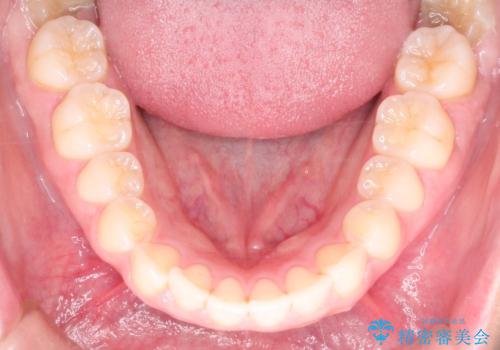

【インビザライン】前歯が出ているのを治したい

- 前歯が出ていることを主訴に来院されました。

前歯の突出感が改善され、満足していただきました。